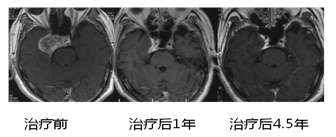

立体定向放射外科的发明人是神经外科医生,同样,颅内肿瘤也是立体定向放疗的主要适应症。而射波刀是颅内肿瘤最佳立体定向放疗手段,也是当前颅内肿瘤的的顶级治疗手段之一。因为射波刀颅骨追踪的优势,使射波刀治疗极为精准。同时,射波刀治疗颅内原发肿瘤和转移瘤不像其他立体定向放疗需要颅骨打孔等,射波刀治疗准备没有创伤。再有,射波刀可以分多次治疗,减轻了治疗副反应。射波刀对于颅内肿瘤的控制率在97%以上。对于颅底,脑干等手术切除难度较大或者手术禁区,射波刀可以大施拳脚,发挥优势,有效控制肿瘤,挽救患者生命。对对于海绵窦血管瘤等无法手术颅内病灶,射波刀更是当前主流治疗手段。对于垂体瘤,颅内动静脉畸形,三叉神经痛等病变,射波刀也可以发挥优异的疗效。

图6 颅内海绵状血管瘤射波刀治疗(治疗后病灶基本消失,患者症状完全缓解,连续复查4.5年没有复发,引自Wang X, et al.)